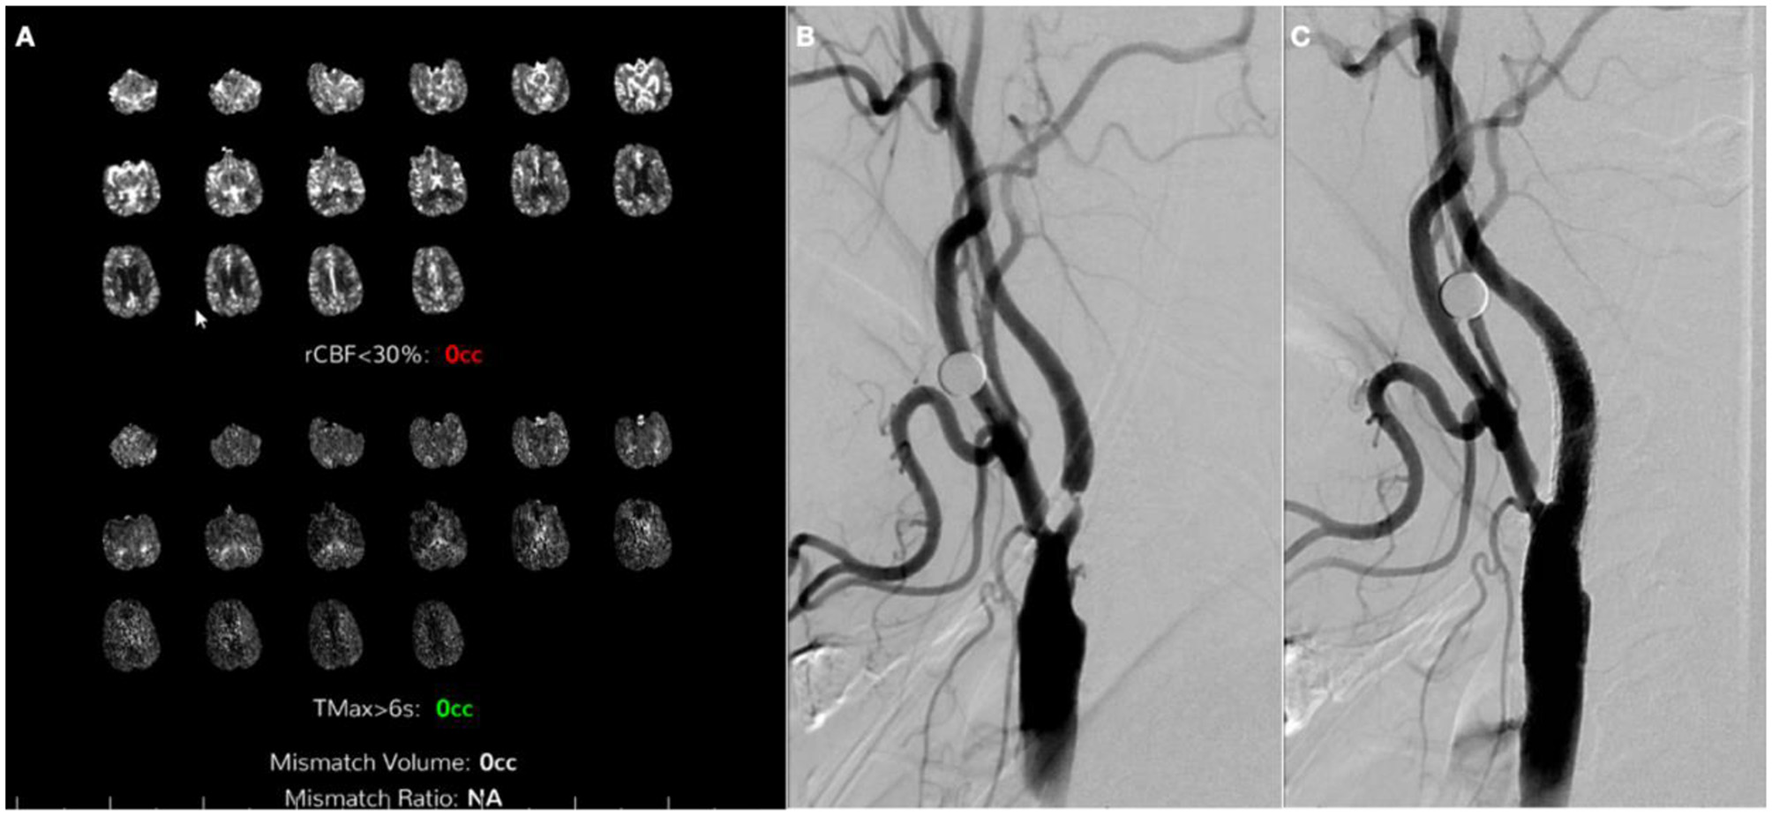

Four weeks after the first procedure, the patient was readmitted for the second stage of stenting. There was interval clinical improvement with only residual minimal aphasia. The patient finally underwent left ICA stenting without complications (Figure 5). On a 90-day follow-up assessment, the patient continued to improve to full resolution of previous weakness and speech impairment and was able to resume their previous activities.

Figure 5. Computerized tomography perfusion (CTP) and digital subtraction angiography 1 month after contralateral stenting. (A) CTP 28 days after right internal carotid artery stenting showing no core or penumbra on left middle cerebral artery territory; (B) Left common carotid artery (CCA) injection, neck lateral view pre-stenting; (C) Left CCA injection, neck lateral view post-stenting.